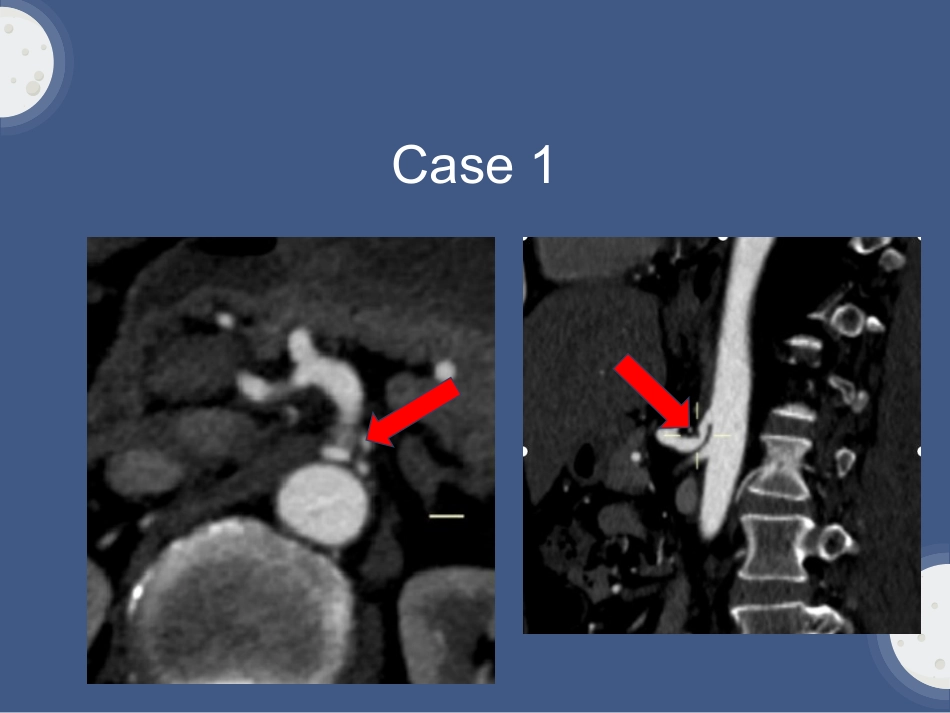

Case1患者,谢XX,男,57岁。因“腰部伴双下肢疼痛,站立行走困难8天”于2018年7月11日入院。既往体健,否认三高。查体:脊柱四肢未见畸形,L1-L4棘突及棘突间压痛,轻叩痛,双下肢肌张力正常。双侧股神经牵拉试验(+)。Case1因止痛效果差,为了排除主动脉性病变,完善主动脉CTA。(P373338)。见PACS系统。Case1Case1•CTA表现:冠状位/矢状位可见:腹腔干起始部前上方明显的“V”型凹陷外压改变,狭窄远端扩张。正中弓状动脉综合征一、疾病概述二、解剖基础三、发病机制四、病理生理五、临床表现六、辅助检查七、鉴别诊断正中弓状动脉综合征CeliacarterycompressionsyndromCACS各种原因导致腹腔动脉外在压迫,导致肠系膜缺血,从而引起餐后腹痛、体重减轻、恶性呕吐等一组后正确。常见外压因素包括正中弓韧带、膈肌脚纤维、神经组织等。别称:中弓韧带压迫综合征MedianarcuateligamentsyndromeMALS腹腔动脉索带综合征CeliacbandsyndromeCBS疾病概述解剖基础•中弓韧带:连接两侧膈脚的纤维韧带,构成主动脉裂孔的前缘;通常位于腹腔动脉起始部上方。•腹腔动脉:起源于腹主动脉前壁主要分支,位于T11-L1间。发病机制•某些先天遗传因素导致腹腔动脉和中弓韧带相对位置的变异进而引起压迫症状。腹腔动脉在主动脉发出位置过高中弓韧带插入位置较低腹腔动脉压迫发病机制•示意图:中弓韧带综合征患者的中弓韧带位于腹腔动脉的前方中弓韧带综合征患者的侧位片,腹腔动脉受压病理生理①外压理论:外压压迫引发的内脏缺血。•腹腔动脉受压+侧枝循环不足系膜缺血(导致疼痛)②神经源性刺激:腹腔神经丛或神经节压迫•腹腔神经丛刺激内脏血管收缩引起交感神经纤维直接激惹刺激(导致疼痛)。临床表现仅10%-24%出现内脏缺血临床表现。年龄:各年龄段均可发病,以40-50岁女性多见。典型症状:慢性剧烈上腹痛(餐后多)——膝胸位缓解。不典型症状:锐/钝痛、绞痛,性质各异,恶性、呕吐。病程:多较长,反复发作、缓解。临床表现主要体征:瘦长体型+肋弓角狭小者居多(疼痛长期畏食致恶性循环)上腹部血管杂音(深呼气明显)辅助检查①介入导管血管造影(DSA)——金标准动态观测、综合评估。②CT动脉血管造影(CTA):首选无创、薄层重组、MPR、VR图像提供有效信息。③磁共振血管造影(MRA):可选用碘剂过敏首选,但腔内病变识别不如CTA④超声多普勒:简便快捷——最常用流速、峰值的测定,定量CTA表现CTA作为常见检查方法:①吸气末检查,腹腔干受压(正常人群15%呼气末可能受压,无临床症状,意义不大)。②腹腔干起始部前上方明显的“V”型凹陷外压改变,狭窄远端扩张,呈典型“钩状”形态。③肠系膜上动脉与腹腔干侧枝循环建立。④可伴有近段、远段多发粥样斑块形成。⑤矢状位重组是评估腹腔动脉起始部狭窄的最佳位置。CTA表现CTA作为常见检查方法:①吸气末检查,腹腔干受压(正常人群15%呼气末可能受压,无临床症状,意义不大)。②腹腔干起始部前上方明显的“V”型凹陷外压改变,狭窄远端扩张,呈典型“钩状”形态。③肠系膜上动脉与腹腔干侧枝循环建立。④可伴有近段、远段多发粥样斑块形成。⑤矢状位重组是评估腹腔动脉起始部狭窄的最佳位置。轴位不同程度的受压表现冠状位/矢状位不同程度受压表现,远段血管扩张容积再现VR诊断要点1、慢性腹痛,特别是餐后腹痛,且能排除其他因素。2、典型影像学表现(冠状位/矢状位)。3、本例临床需做好其他疾病的排除性诊断。鉴别诊断粥样斑块鉴别诊断大动脉炎狭窄:多为向心性狭窄,并可见多跟动脉受累;如诊断困难时可采用呼吸变化扫描法判断对狭窄程度的影响。Theend